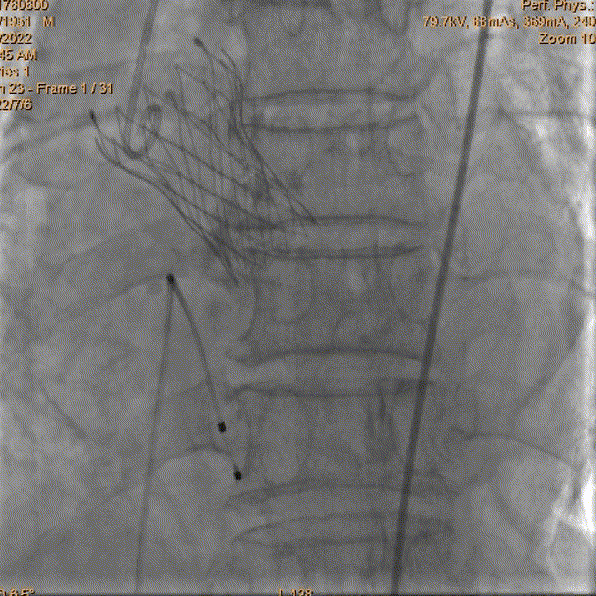

瓣膜最终释放位造影

即刻跨瓣压差0mmHg